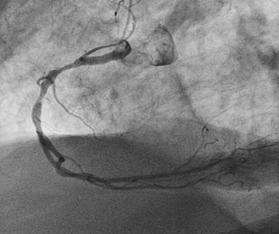

A 81year old gentleman presented to the emergency department accompanied by emergency physician and paramedics with typical angina symptoms for last 1hour associated with Dyspnoe, nausea  and vomitimg. The chest pain has subsided with administration of Morphin i.v. On arrival in the emergency department, one immediate 12-lead ECG  was done, that showed lateral wall  ST-elevated myocardial infarction (Figure 1). Wihout delay as per the current guidelines one emergency  angiogram was done, that revealed one occluded Ramus diagonalis branch of Left anterior descending artery(Figure-2) and one Plaque rupture in mid segment of right coronary artery with subtotal occlusion (Figures 2 & 3). Immidiately the coronary flow in Ramus diagonalis -2 was regained and the culprit lesion was treated with 2 drug eluting stents  2,25X14mm size, the end result was TIMI III Flow in Ramus diagonalis -2. During the procedure the EKG showed ST elevation in lead II, III and aVF with intermittent Atrioventricular Block III, Blood pressure was 100/56mm Hg and heart rate was 65 per minute. We decided to perform the angioplasty of Right coronary artery. The flow in right coronary artery was restored and the culprit lesion as treated with 2 Drug eluting stents 3.0X19 mm and 3,5X 14mm, resulting in TIMI III Flow. The ST elevation leads II, III and aVF were settled.

Figure 2 Coronaryangiography.